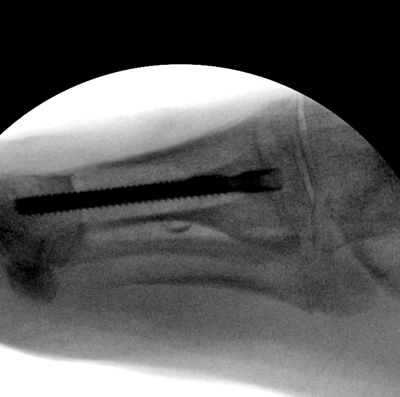

TOTAL ANKLE REPLACEMENT :: ORIF CALCANEUS :: ORIF ANKLE FRACTURE DISLOCATION :: COMPLEX BUNION AND LESSER TOE CORRECTION :: TALUS FRACTURE -1 :: TALUS FRACTURE -2 :: LISFRANC REPAIR :: COMPLEX TRIPLE ARTHRODESIS 1 :: COMPLEX TRIPLE ARTHRODESIS 2 :: MINIMALLY INVASIVE BUNION REPAIR 1 :: MINIMALLY INVASIVE BUNION REPAIR 2 :: ARTHROSCOPIC CARTILAGE REPAIR :: TENEX SPUR DEBRIDEMENT :: Haglunds Debridement and Achilles Repair